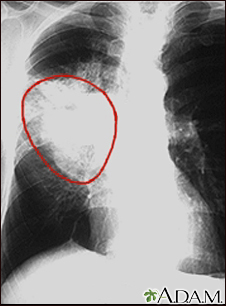

Lung cancer - frontal chest x-ray